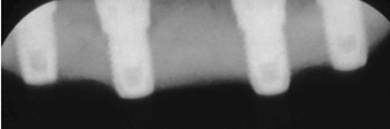

The Toronto Conference in 1982, chaired by Professor George Zarb and presented by Professor Per-Ingvar Brånemark, was a seminal event that changed edentulous treatment planning concepts irrevocably. No longer was it necessary to rebuild lost bone through grafting alone in either arch. The severely atrophic mandible, for example, could be treated with as few as four implants used to support a bone-sparing prosthesis through integrated tooth analogs, as demonstrated in Figure 1 through Figure 3. Here, an 81-year-old patient presented with severe mandibular atrophy (Figure 1) from denture wear since a very young age and had a history of being unable to manage a mandibular prosthesis despite numerous attempts at new denture construction. Four vertical machined-surface osseointegrated implants were placed in 1983 by Professor Brånemark, and all four penetrated the inferior cortex up to 3 mm to 4 mm in depth, as shown on the immediate postoperative panoramic film (Figure 2). At 4 years and 5 months, reparative bone had formed to the apices of all implants (Figure 3), and all of them remained in uncompromised function until the patient passed away at age 90.

Fig 2. Four vertical machined-surface osseointegrated implants placed in 1983 penetrated the inferior cortex up to 3 mm to 4 mm in depth, immediate postoperative.

Figure 2